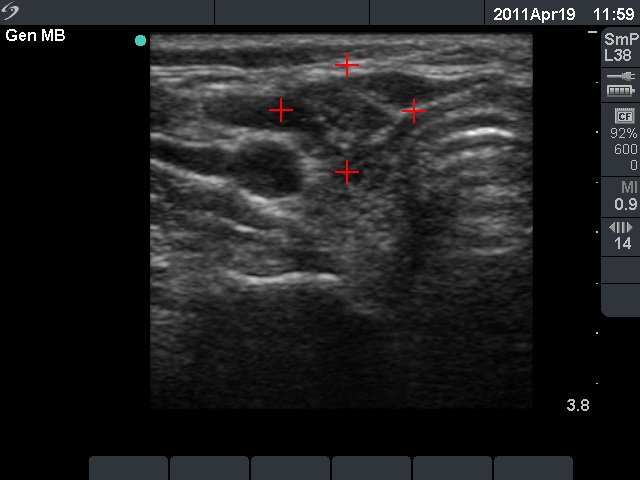

Granulation around surgical thread (cytological diagnosis) - case 981

The granulation pointed with calipers is located within the sternocleidomastoid muscle .